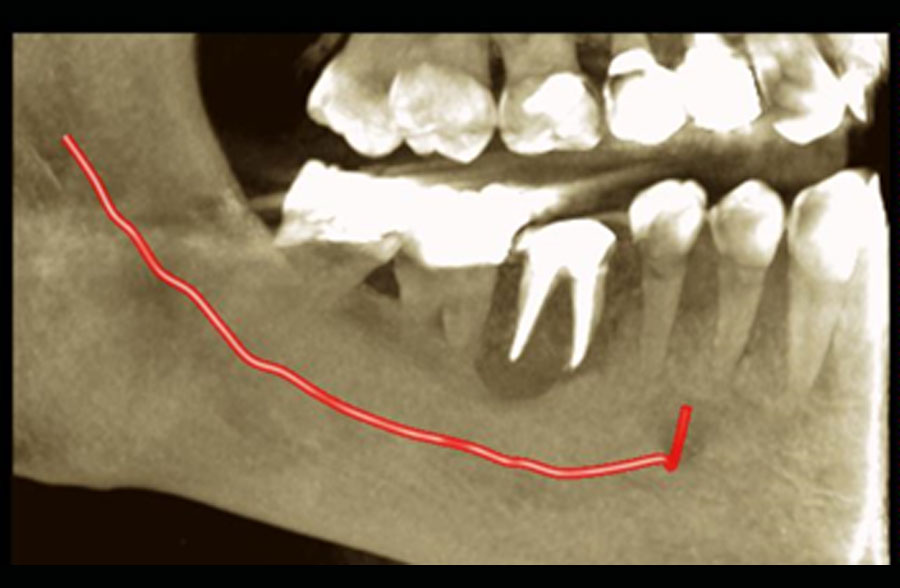

Σήμερα, στο «οπλοστάσιό» μας, έχει προστεθεί και η υπολογιστική τομογραφία κωνικής δέσμης (CBCT), οι εικόνες της οποίας είναι ιδανικές τόσο για να μας πληροφορήσουν για τη μορφολογία του συστήματος των ριζικών σωλήνων αλλά κυρίως να μας βοηθήσουν στη διάγνωση των βλαβών στο άκρο της ρίζας, στην έκταση αυτών των βλαβών και τη σχέση τους με παρακείμενες ανατομικές δομές (π.χ. ιγμόρειο).

Δυστυχώς υπάρχουν περιπτώσεις όπου η νεκρωτική βλάβη του πολφού ενός δοντιού, συνοδεύεται από έξοδο των μικροβίων από το σηπτικό ριζικό σωλήνα στους περιακρορριζικούς ιστούς. Η χρόνια ακρροριζική περιοδοντίτιδα όταν χαρακτηρίζεται από μεγάλες δομικές αλλοιώσεις των περιακρορριζικών ιστών, μεγάλη απορρόφηση του φατνιακού οστού που στηρίζει το δόντι, δεν μπορεί να αντιμετωπιστεί πάντα με τη συντηρητική ενδοδοντική θεραπεία του υπαίτιου δοντιού.

Προκειμένου να παραμείνει το δόντι λειτουργικό στο φραγμό και να μη προβούμε στην αφαίρεσή του, προσπαθούμε να συνδυάσουμε την ενδοδοντική θεραπεία με τη χειρουργική αφαίρεση όλων των παθολογικών στοιχείων που εντοπίζονται στους περιακρορριζικούς ιστούς. Η μικροχειρουργική επέμβαση πραγματοποιείται από τον γναθοπροσωπικό χειρουργό κ. Βήλο Γιώργο.